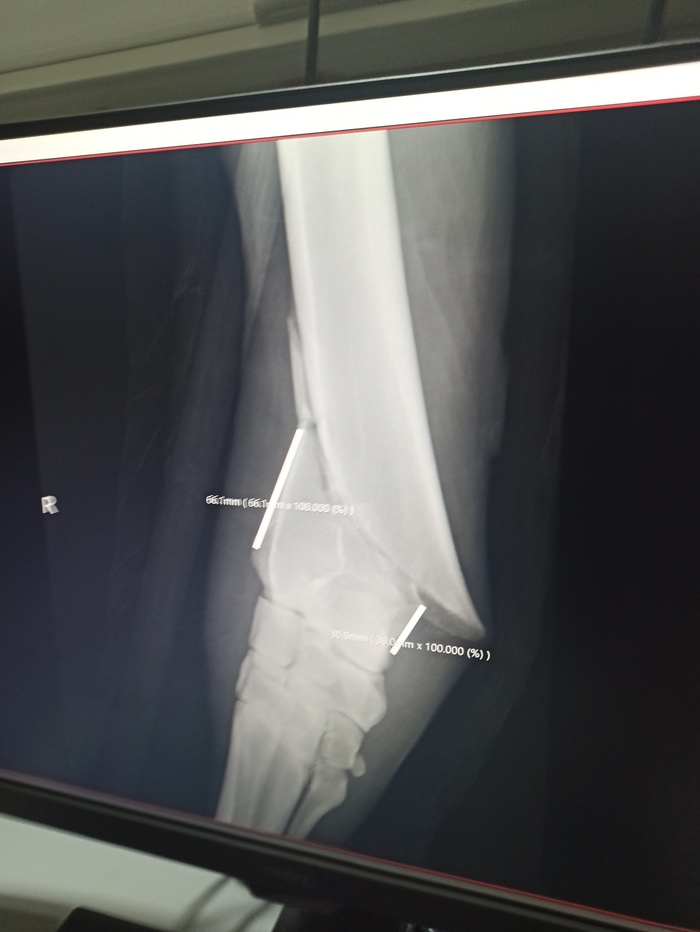

Идём смотреть рентгены. Перелом плохой, есть крупный осколок, смещение. Линия перелома заканчивается очень близко к костям запястья. На то, чтобы закрепить пластину, есть буквально три сантиметра. Это чрезвычайно мало, и неизвестно, выдержит ли пластина нагрузку при таком креплении. Но больше места нет. "Выживаемость при таких переломах 3-5%". Сердце пропускает удар. До этого мне говорили, что шансы несколько выше. И уже тогда это звучало страшно. Но 3-5%... "Я. Всё равно. Хочу попробовать".

"Выведете его?". Не сразу понимаю, что вопрос адресован мне. "Да, конечно". Пытаюсь развязать чомбур. Бесполезно, руки не слушаются. В конечном итоге справляюсь с узлом и выхожу из денника. Милорд идёт за мной. Ну как, идёт. Подставляет под корпус задние ноги как можно ближе к передним и, перенося вес назад, толкается левым передом, переставляя ноги вперёд. И так каждый шаг. Ему тяжело и больно. Каждые три таких шага ему нужен отдых. Он останавливается, немного отдыхает, и снова следует за мной. Пытается отдышаться в перерывах. Четыре таких остановки и мы пришли к боксу. Перед заходом в бокс делают ещё несколько рентгеновских снимков. "Ещё чуть-чуть и перелом будет открытым". Заводим в бокс, ставим головой в сторону операционной, корпусом вдоль стенки. Недоуздок крепят повыше и продевают корду в один из ремней. Вторую корду продевают в заплетëнный хвост. "Не переживай, скоро ты уснёшь и больно не будет". Постепенно наркоз начинает действовать, мышцы расслабляются, Милорд оседает на пол. Корды не дают ему упасть, его аккуратно укладывают на бок. Уснул. Затем переворачивают на спину, ноги оборачивают верёвками. Подвешивают за ноги на огромный крюк, поднимают краном и транспортируют в операционную. "Вам лучше пойти посидеть в кафе, операция долгая, часа четыре. Здесь Вы будете нервничать, там будет немного спокойнее". "Мне же позвонят, если что-то пойдёт не так?" - всё ещё помню, что только в процессе операции станет ясно, получится ли собрать ногу. "Позвонят".